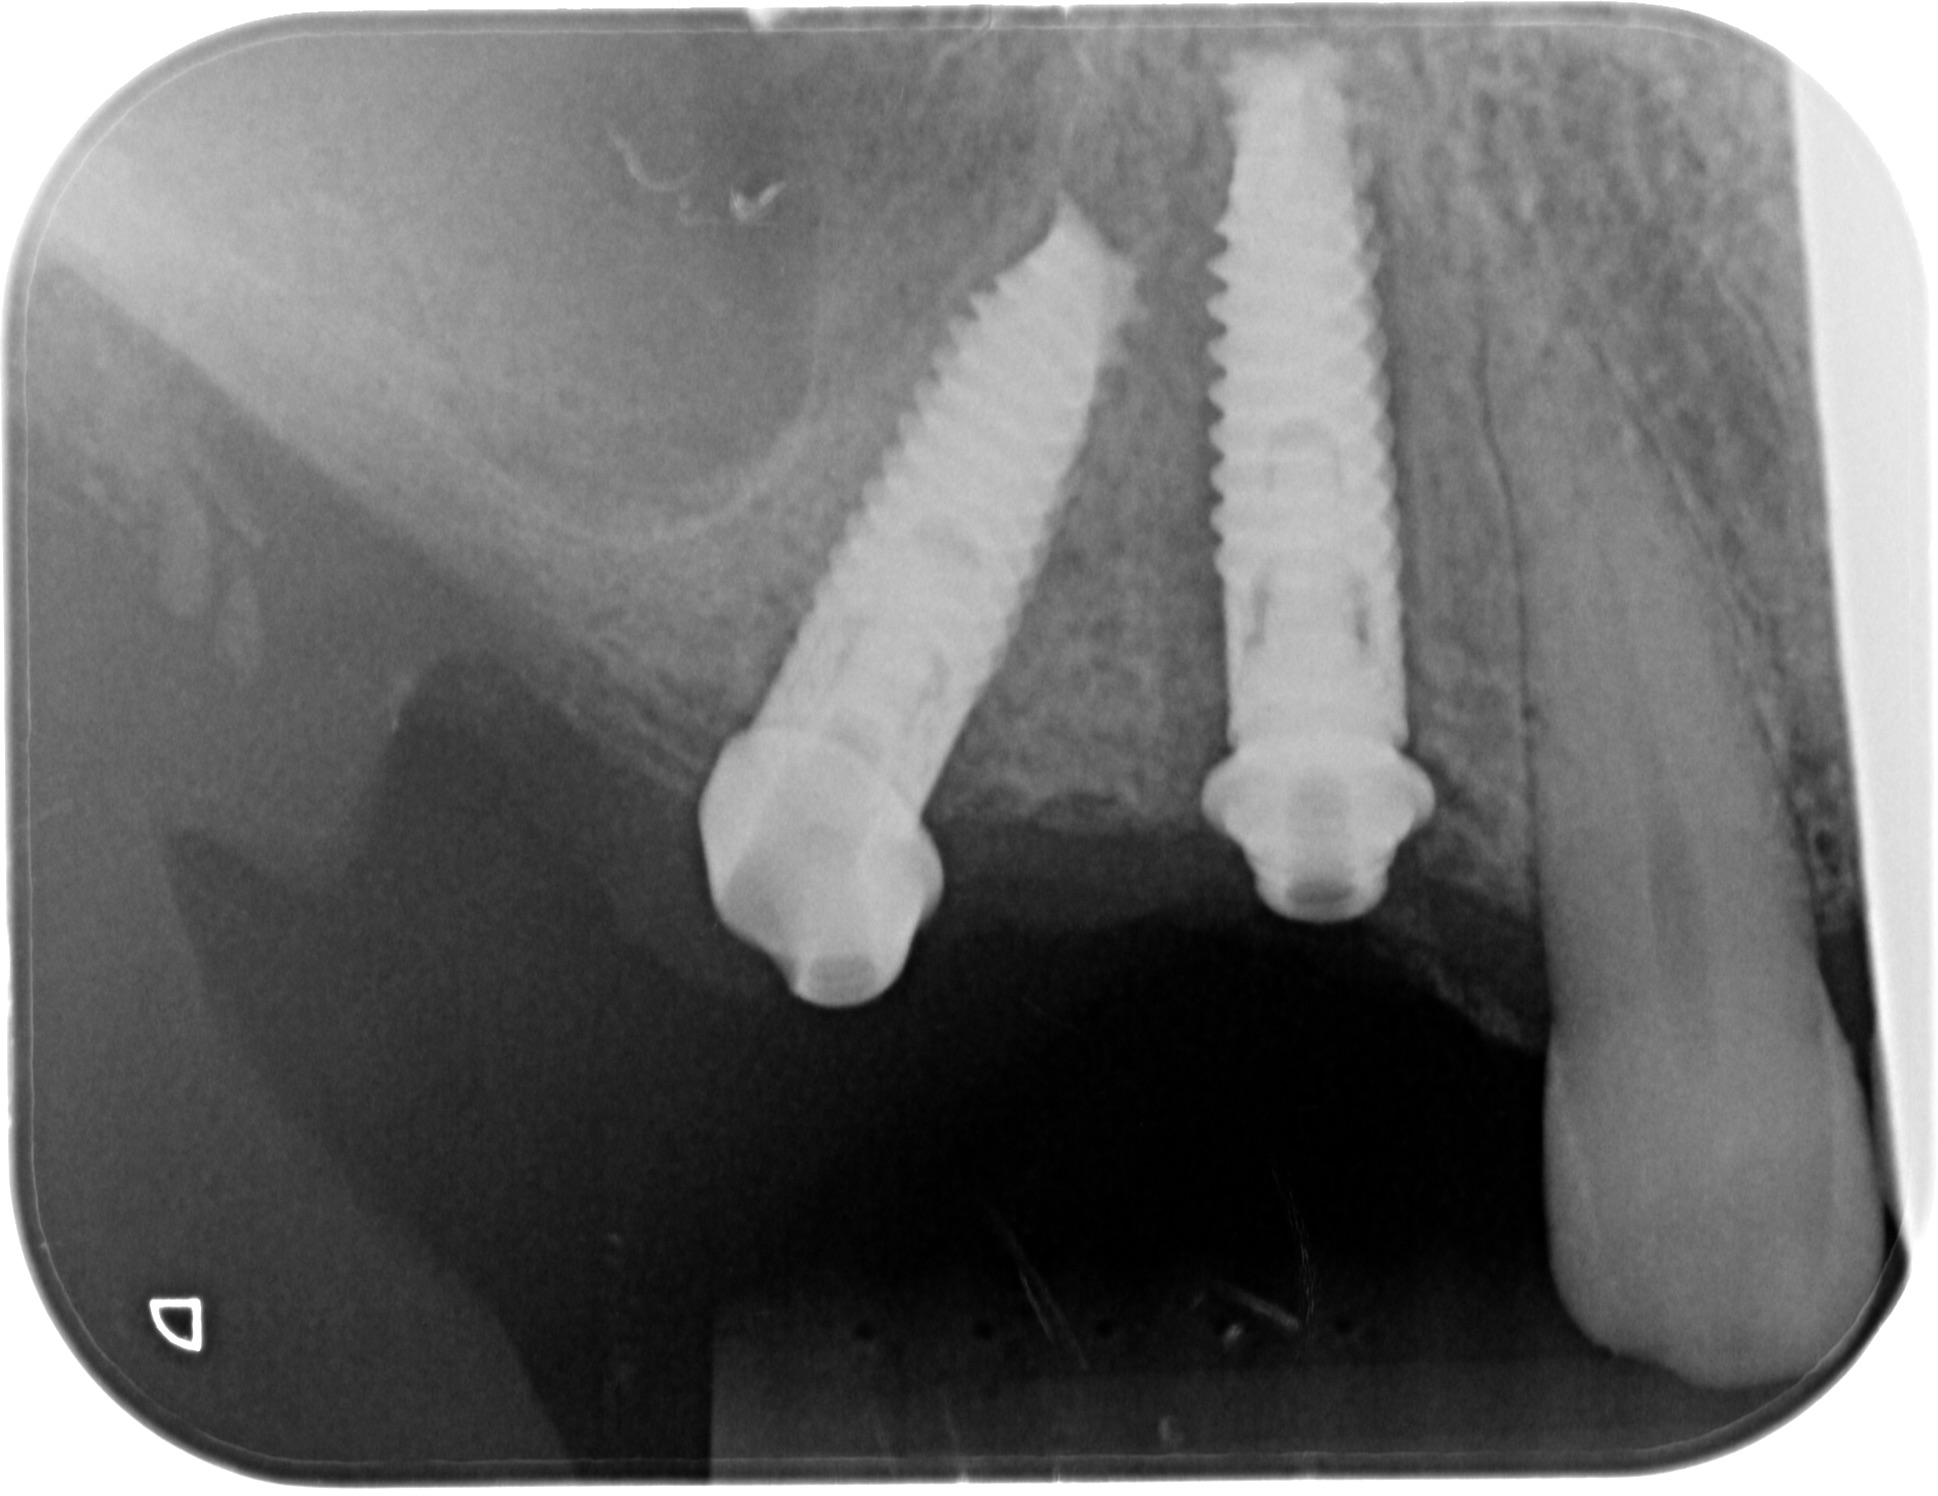

Рис.4- рентгенограмма установленных имплантатов V3 (Mis implant).